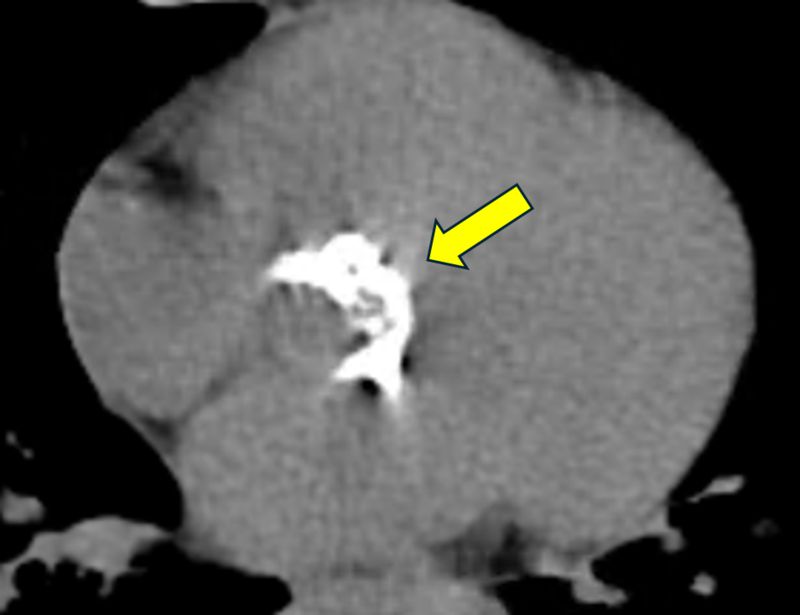

主動脈瓣由三片瓣葉構成,心臟收縮時開啟,放鬆時閉合,防止血液回流。若瓣膜退化因肥厚、鈣化無法正常開合,因此影響全身血流血流,即為「主動脈瓣狹窄」。一般而言,重度主動脈瓣膜狹窄多見於70歲以上病人,而年輕如陳女士般尚未50歲就發生嚴重鈣化與狹窄的多是先天性雙瓣的主動脈瓣者。楊凱文醫師指出,先天性雙瓣主動脈瓣膜的患者在中年即容易出現瓣膜狹窄或閉鎖不全,並伴隨主動脈擴大的問題。國外統計指出,約有40-60%的雙瓣主動脈瓣患者會出現主動脈瘤或主動脈擴大情形。

楊凱文醫師指出,重度主動脈瓣膜狹窄的病人,唯一治療方式就是開刀置換主動脈瓣,無法僅靠藥物控制。目前的手術方式有開心手術與經鼠蹊部導管置換主動脈瓣手術兩種,由於病人合併有主動脈瘤且不符合後者的健保適應症,醫療團隊以開心手術的方式替其治療。特別的是,傳統開心手術需劈開整塊胸骨,傷口可達15至20公分,但楊凱文醫師採J型鋸開胸骨,以僅約6公分的傷口,將已經鈣化的瓣膜組織完整切除,接著處理主動脈內部殘留的鈣化區塊,進行去鈣化和壓碎處理。之後,植入一枚新的人工生物瓣膜。同時,將動脈瘤的部分一併切除,再以手縫方式接上人工血管,完成修復。由於陳女士不希望長期服用抗凝血藥物,因此選擇植入新一代的生物瓣膜,雖然生物瓣膜僅有約10至15年的壽命,但未來若瓣膜退化,可透過微創導管手術直接置換新瓣膜,無需再次開胸,大幅降低風險。